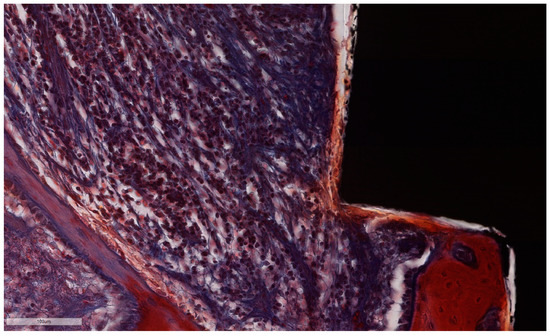

Figure 10. In the absence of the ligature, full epithelial lining is observed along the interface with the implant, with no ulceration. Note the intimate contact between the soft tissues and implant surface that coronally ends above the level of the BC, while the ICT remains above the BC-BD line. (implant #2, MGA, bar measure is 700 µm).

Figure 13. ICT in direct contact with the implant surface, without an interposed epithelial lining. Note the abundant lympho-plasmocytic infiltrate, which progresses inside the bone marrow, the thin bone trabeculae left after remodeling along with prominent osteoblast rim (implant #3, MGA, bar measure is 100 µm).